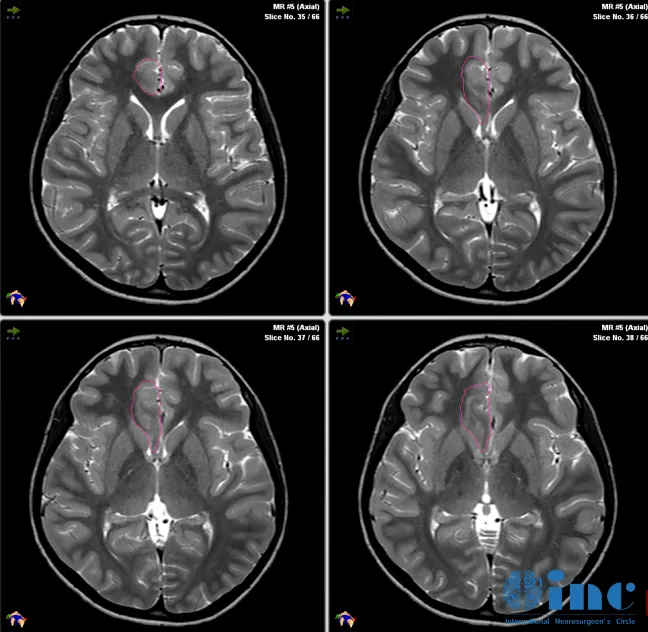

12岁的男孩Jason患有额叶癫痫,伴有运动机能亢进的癫痫发作,神经成像检查结果显示:右侧额内侧下基底病变。为了治好孩子的额叶癫痫,Jason父母决定让孩子接受开颅右额叶病灶切除术,病理资料显示为局灶性皮质发育不良(FCD),术后三个月无癫痫发作。

然而非常不幸的是,三个月后Jason的癫痫复发了,但是考虑到孩子年纪尚小,太短时间内再次接受开颅手术可能会造成术中或术后损伤,于是找到INC加拿大Rutka教授,希望教授为Jason进行不开颅的LITT治疗。

在MRI引导技术,教授团队清晰地识别病灶与周围健康脑组织的位置关系,进而制定精确的手术路径,成功消融了Jason脑内残余的病变组织。

LITT手术后Jason很快便出院了,之后他便没有癫痫发作了,而且近期随访显示其生长发育和智力发育正常,而且癫痫并未复发。